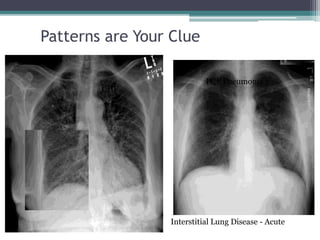

• Patterns are your clue

Patterns are Your Clue

Interstitial Lung Disease - Acute

PCP Pneumonia

CHF

Patterns are YourClue Interstitial Lung Disease - Acute PCP Pneumonia CHF